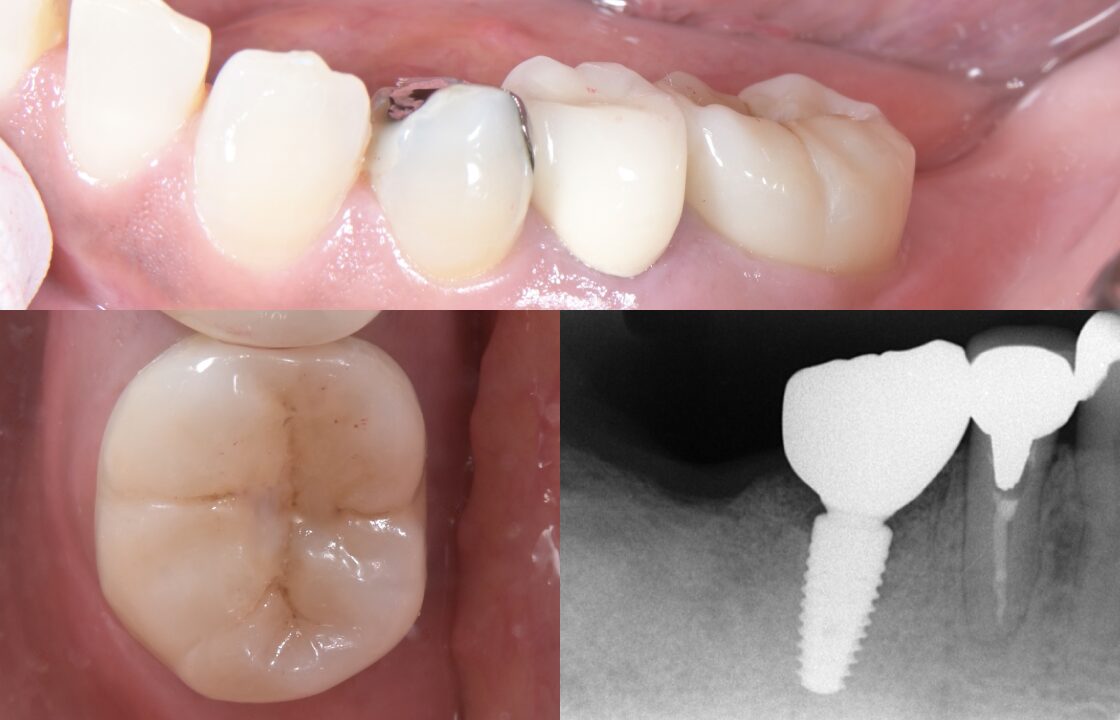

歯根破折により抜歯を要した症例への即時埋入インプラント治療

- 治療内容

- 歯根破折により保存不可能と診断し、抜歯即時埋入によるインプラント治療を行いました。

インプラント埋入前に、iOS(口腔内スキャン)データとCTデータをシミュレーションソフト上でマッチングし、埋入ポジションを決定。サージカルガイドを作製し、ガイデッドサージェリーにてインプラント手術を行いました。デジタルをインプラント治療に取り入れることで治癒期間の短縮と解剖学的形態の獲得を達成できました。また最終補綴物はジルコニアクラウンをスクリューリテイニングにて行うことでメンテナンスを容易にすることもできました。

- 3ヶ月

- 治療費用

- 60万

- 治療のリスク

- 抜歯窩とインプラントとのギャップが埋入時に生じるため感染させないための処置が重要になる。またメインテナンスを容易にするためにインプラント埋入ポジションがズレないよう慎重な手技が求められる。これらを確実に行わないとインプラントが骨とうまく付かない場合があります。

AFTER